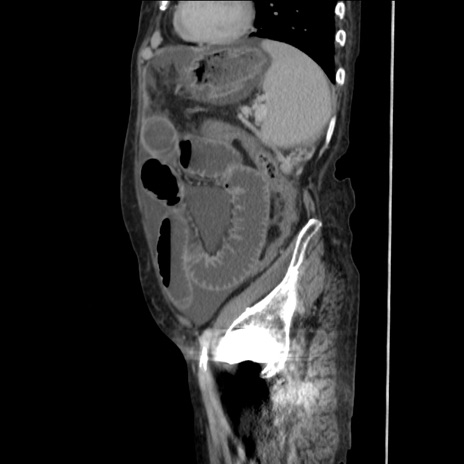

症例31(矢状断像)

【症例】80歳代 女性

【主訴】腹部膨満感

【現病歴】他院にて肝硬変にてフォロー中。1週間前から便秘、腹部膨満感、臍部腫瘤あり受診となる。

【既往歴】肝硬変

【身体所見】腹部膨隆あり、皮膚変化なし、疼痛なし。

【データ】WBC 4600、CRP 0.25